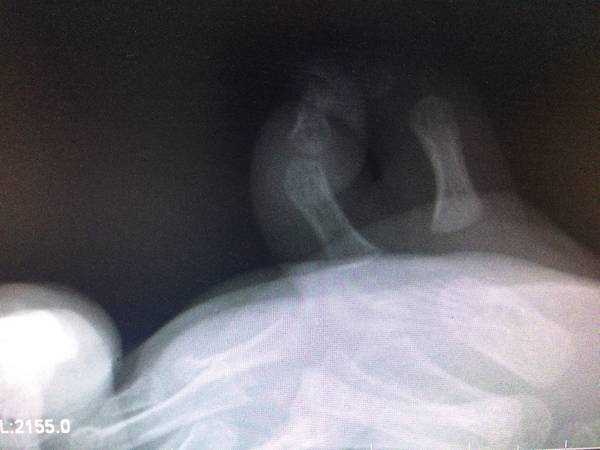

今天做了一台小儿重复拇指畸形患者

按照重庆医科大学附属儿童医院的田晓菲老师和上海九医院王斌教授的指导

进行了部件组装手术

个人觉得手术很成功

微信确实方便,周五收治一名1周岁的重复拇指患儿,入院后拍片发现是VII型多指,手术比预计的复杂多了,而且术后效果不好。幸好有上海九院王斌教授组建的手整形重建外科交流群,小儿先天畸形的国内顶级专家有很多,上海九院王斌教授,上海华山医院的方有生教授,重庆医科大学附属儿童医院的田晓菲教授,还有香港陈德平教授。我把患儿的X线片和手的外观图片发上去后,得到了王斌教授的详细指导,并且发了一组类似的病例图片给我看,告诉我手术注意事项。田晓菲老师更是给出了详尽的分析。昨天晚上夜班,趁孩子睡觉时特意拍照了双手对比的照片,设计了手术方案。今天上午手术按照计划,非常顺利完成了,很为患儿高兴,因为她的手术得到了国内顶级专家的手术指导,相信术后效果应该很好的。交流才会发展,学习才会进步!